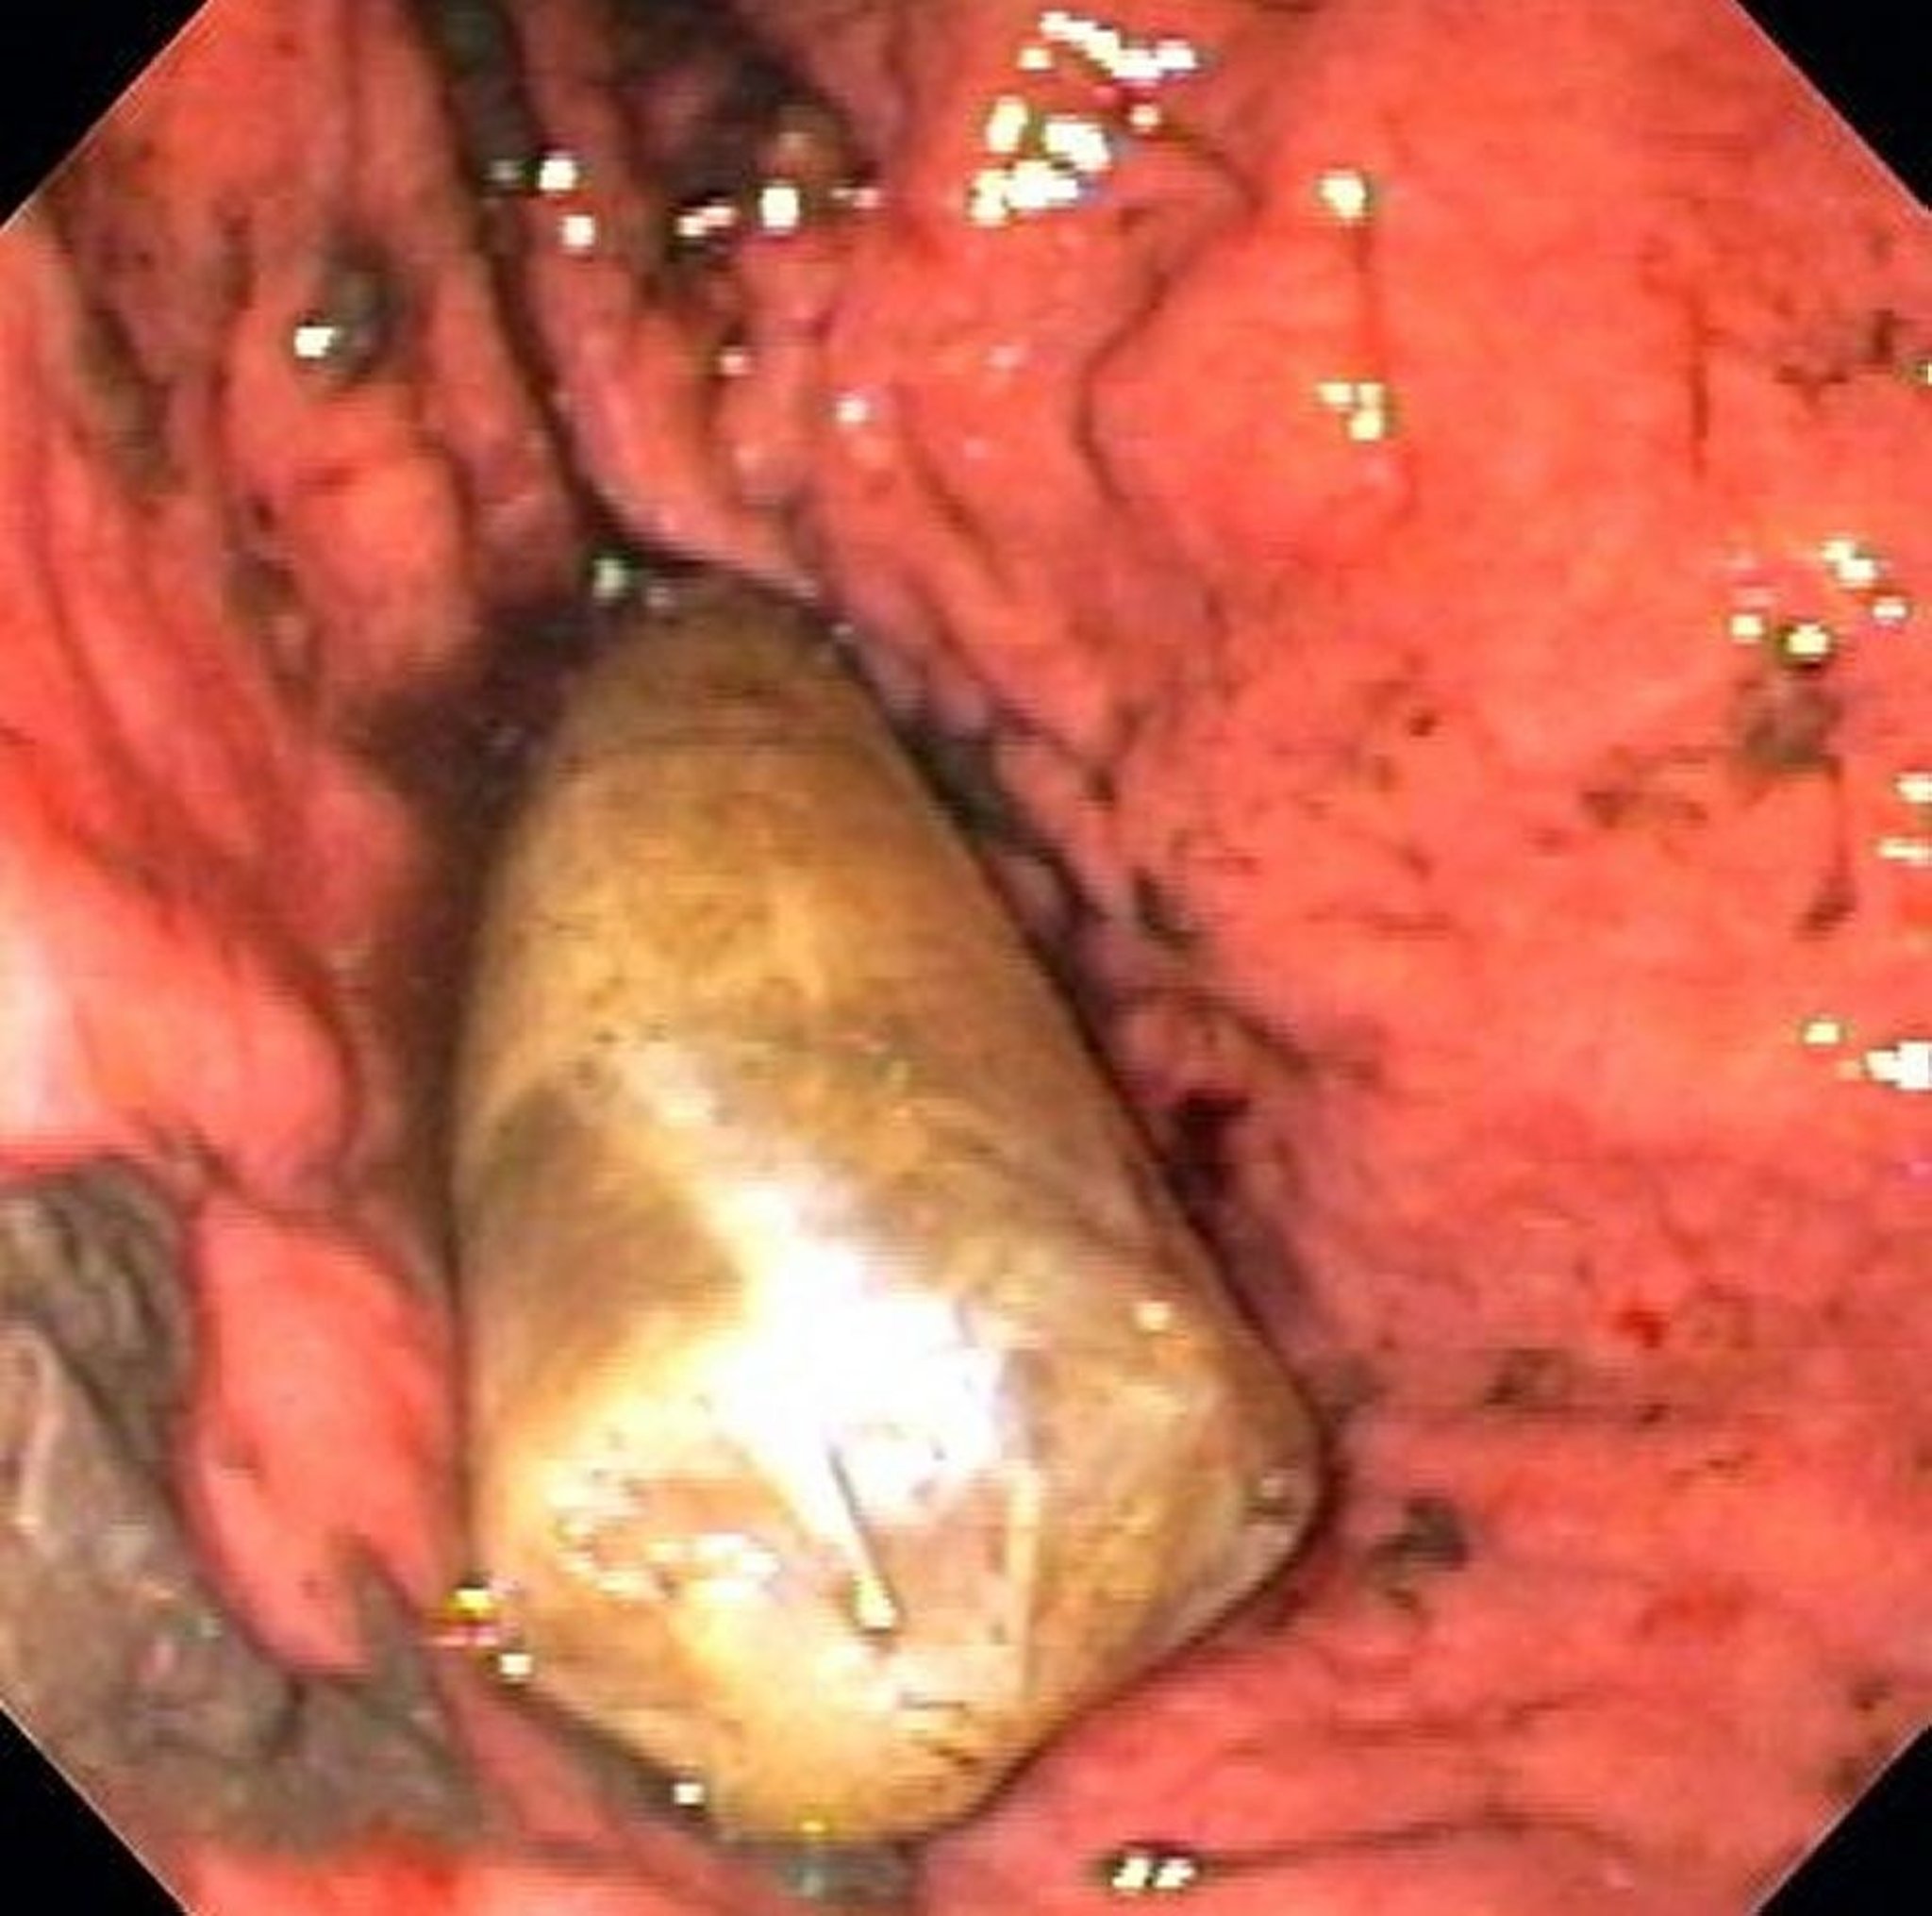

Fremdkörper im Magen (Endoskopie)

Auf diesem Bild ist ein Drogenpaket im Magen zu sehen.

Bild von Alan Gingold, DO.